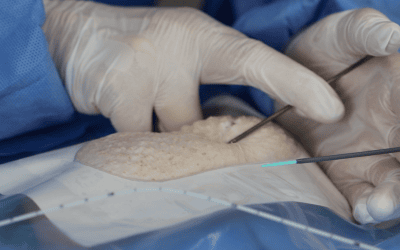

8. Uso de sistema de fijación sin suturas + cianoacrilato + membrana transparente:

Todas las guías internacionales desaconsejan el uso de suturas para la fijación de los catéteres vasculares. La evidencia ha demostrado que las suturas incurren en mayor riesgo de punción accidental del profesional, de mayor riesgo de trombosis y de infección, además de ser incómodas para el paciente, sobre todo, en algunas zonas anatómicas.

Los sistemas de fijación sin suturas pueden ser adhesivos o subcutáneos, siendo estos últimos indicados en pacientes cuyo catéter vaya a permanecer más de 3 semanas o en casos de piel delicada o MARSI, con riesgo de salida accidental o en pacientes no colaboradores (desorientados, niños, neonatos) (imagen 8)

El uso del cianoacrilato en el punto de inserción ayuda a la hemostasia y controla el eventual sangrado post inserción, haciendo que la primera cura pueda realizarse a la semana, en vez de en las primeras 24 horas. Así mismo, el cianoacrilalto funciona como una barrera estéril protectora del punto de inserción durante el tiempo que esté presente.

Para finalizar, el uso de la membrana transparente semipermeable permite una observación directa del punto de inserción y una cobertura efectiva de toda la piel que lo rodea. Es recomendable elegir aquellas membranas con mayor transpirabilidad para el vapor de la piel, de modo que éste no se acumule bajo el apósito y pueda crear maceración cutánea.